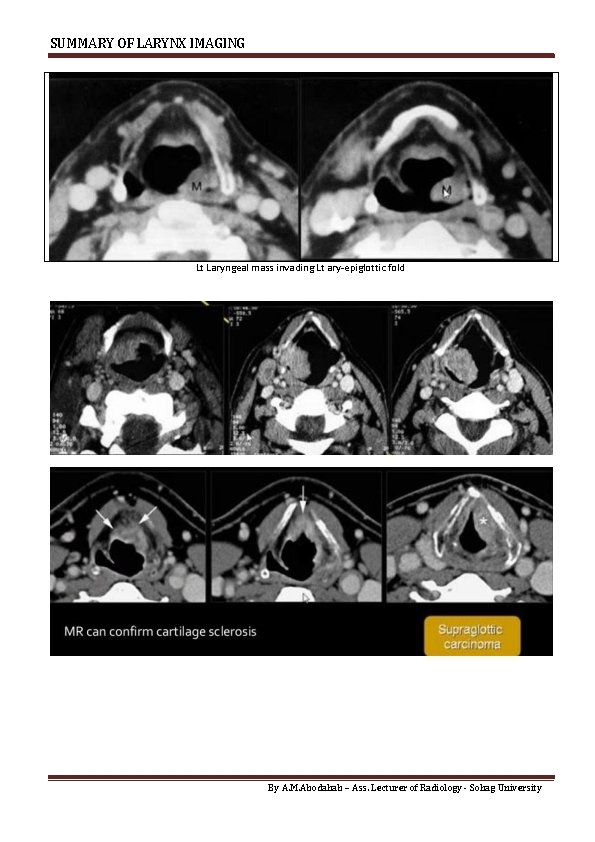

SUMMARY OF LARYNX IMAGING Lt Laryngeal mass invading Lt ary-epiglottic fold By A. M.

SUMMARY OF LARYNX IMAGING Air fluid level in External & Mixed 2. CANCER LARYNX Mostly Squamous cell carcinoma Incidence Supra-glotic 70 : 60 % Glottic 25 : 35% Sub Glottic 5 % Transglottic Involve 3 levels Lymphatic spread 30 % 1% 30 % Role of Imaging : o CT & MRI Assess site & extension of Mass o In supraglottic lesions : Extension to pre epiglottic space & Para Glottic Space & Ant. Commisure By A. M. Abodahab – Ass. Lecturer of Radiology - Sohag University